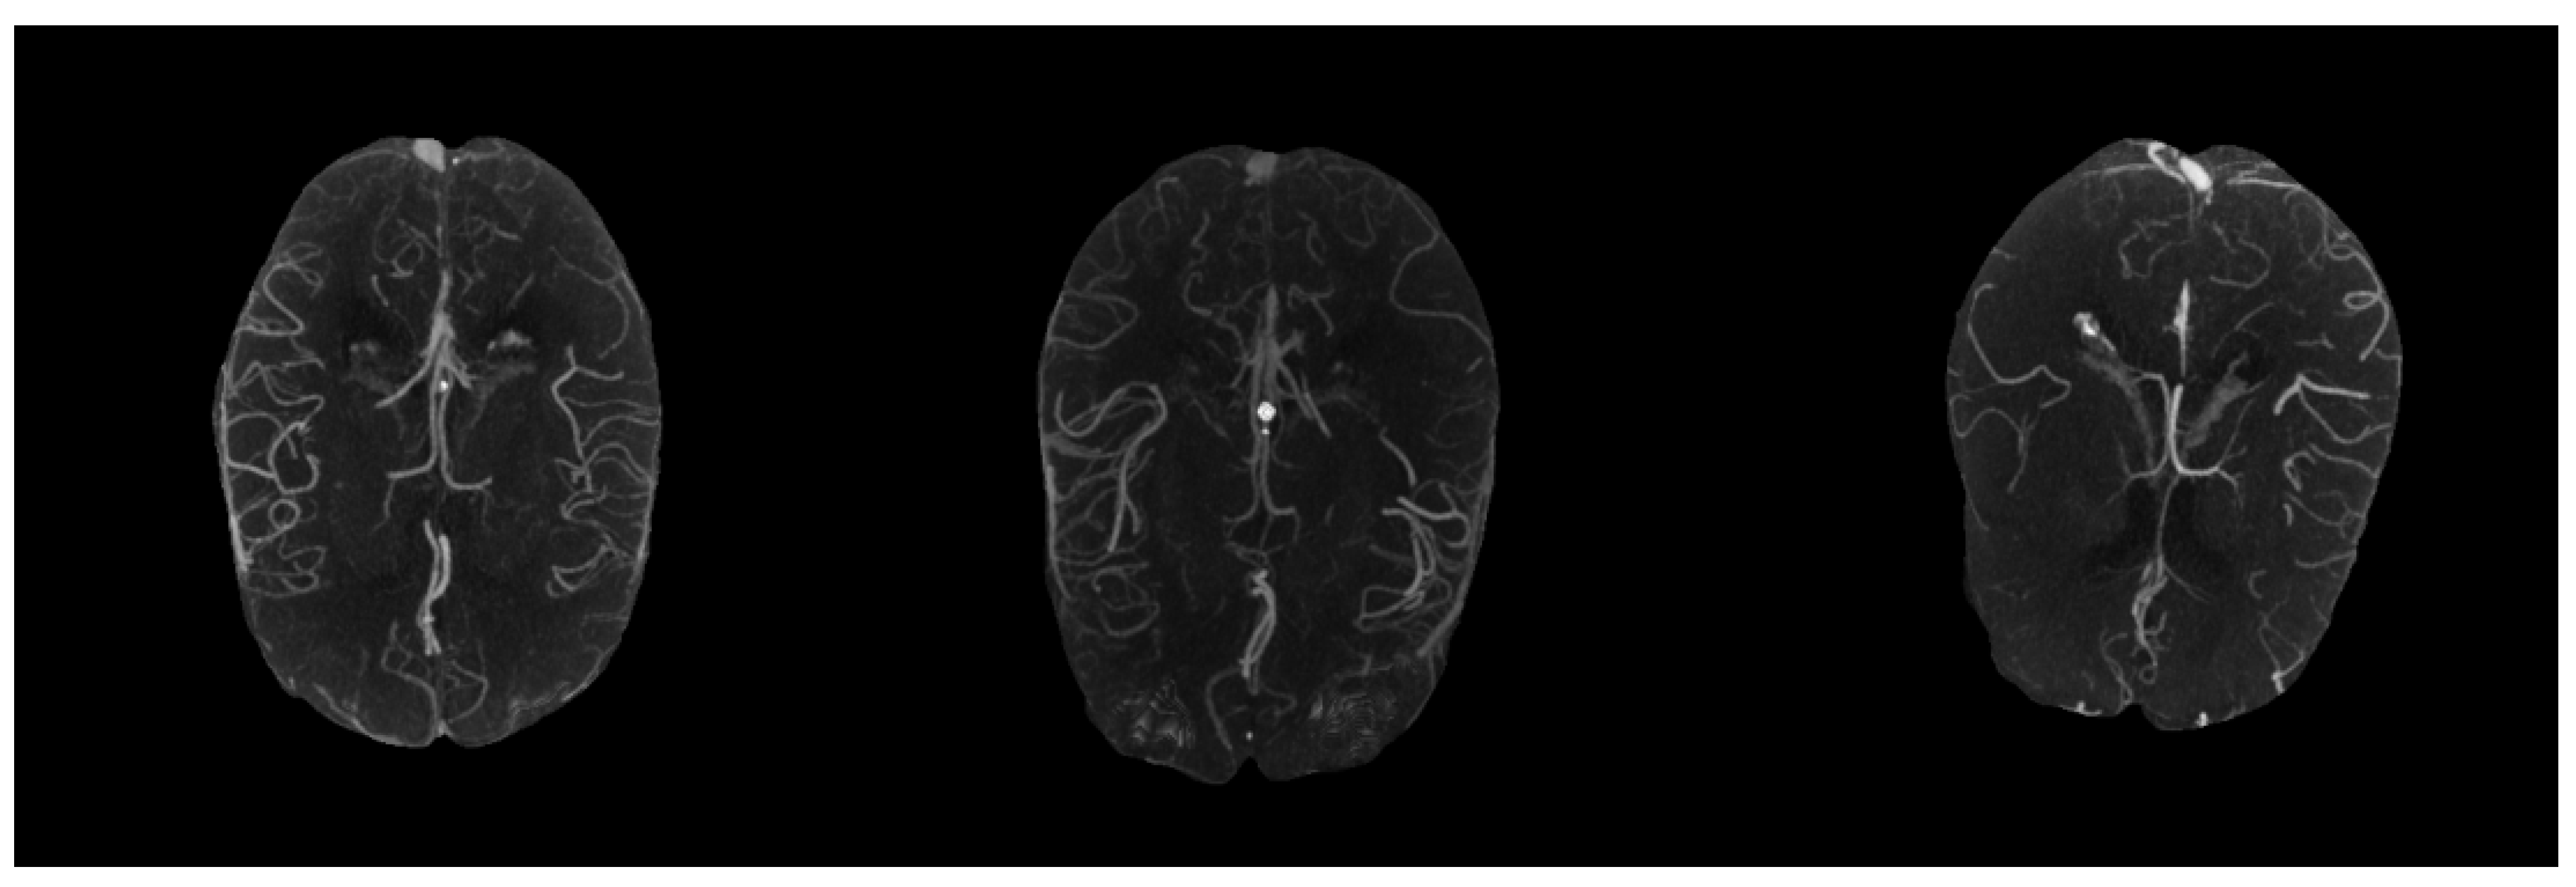

Because the vessel voxels in 3D CTA scans generally had high intensities, maximum intensity projection (MIP) that projected 3D CTA scans to two-dimensional images could well display the degree of stenosis, dilation and filling defect of vessels [21]. Figure 2 shows visualized MIP results of CTA scans with different collateral scores. As shown in Figure 2, after MIP on the whole 3D scans there were significant differences in the degree of collateral filling in patients with different scores, but there existed some interference outside the MCA regions. Additionally, since the vasculature capable of assessing the status of collateral extended from the skull vertex to the circle of Willis, too much irrelevant vasculature would easily interfere with the scoring [28]. Thus, in order to clearly show the vessels in the MCA arterial tree in the left and right hemispheres and reduce the interference from varying numbers of slices, we only took the 30 most-cranial axial slices from the circle of Willis and multiplied the acquired 3D CTA images with the generated MCA masks before performing MIP in the final preprocessing step.

From Figure 2, we found that the vessel regions became more salient in MIP images, making it possible to design a vessel-segmentation free method using MIP images. After performing data augmentation on the obtained MIP images, we used a hybrid deep learning model: the MPViT proposed in [29], which combines Transformer and CNN to capture global and local information at the same time. MPViT first processed the input images through a convolution-based stem module to change the image size to 128 × 128. Then, it utilized four stages to learn effective representations for collateral scoring. Each stage consisted of a multi-scale patch embedding based on convolution with different strides, several Transformer-based blocks (the number of blocks is adjustable) to capture global information, a CNN-based block, and a concatenation layer followed by a 1 × 1 convolution layer to effectively combine features from Transformer and CNN blocks. The classification results were achieved by a global average pooling and a linear layer. For more technical details of MPViT, please refer to [29]. Figure 3 shows the framework of our designed hybrid CNN and Transformer network for collateral scoring.

Figure 2. Examples of maximum intensity projection (MIP) images from 3D CTA image with different collateral scores. The left one is good collateral. The middle one is intermediate collateral. The right one is poor collateral.

Biomedicines 11 00243 g002